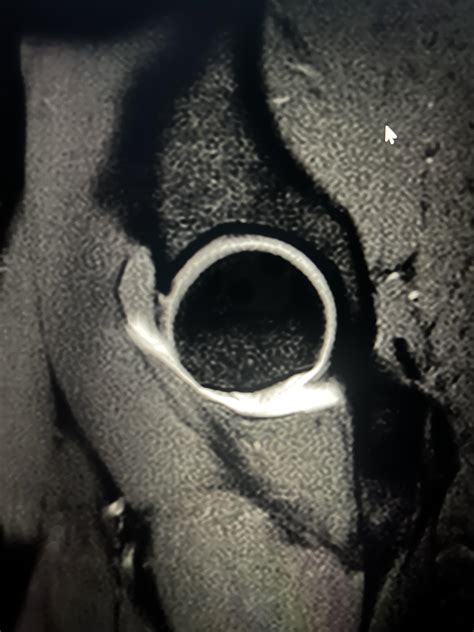

Anatomy Of Labrum at Harry Brawner blog